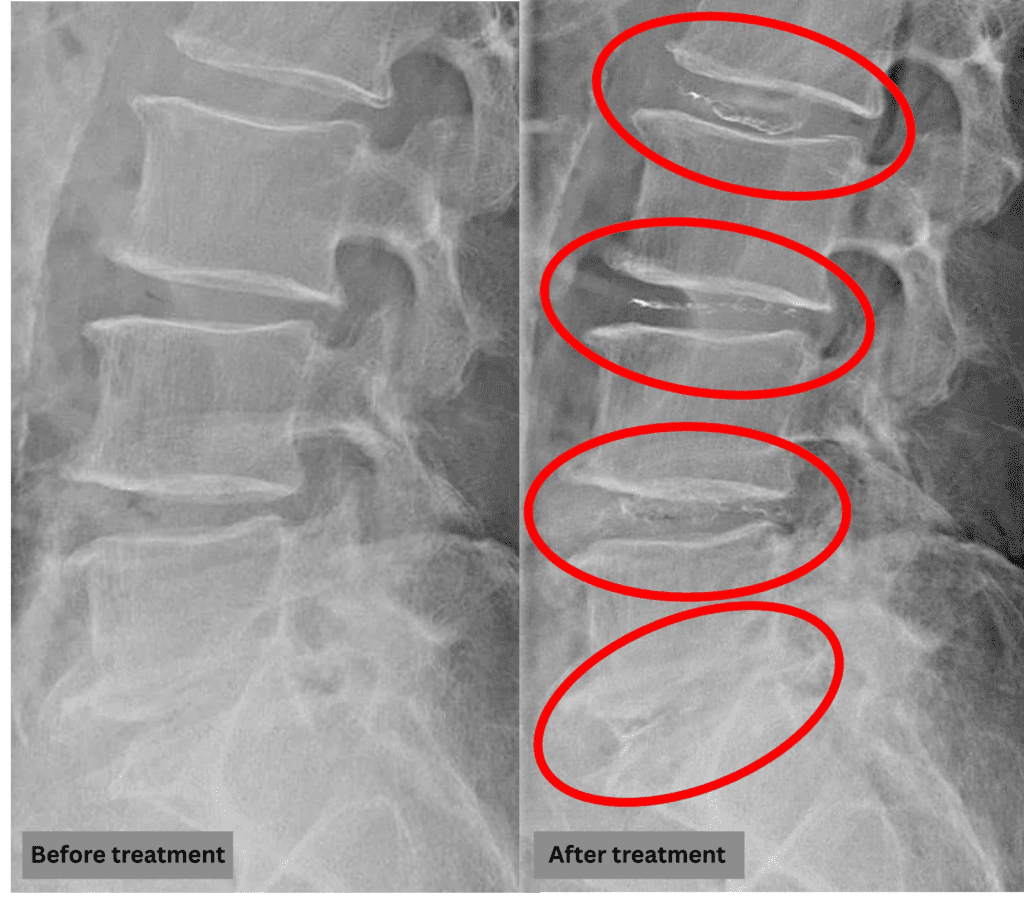

After consulting with the patient, the Cellgel Method was performed on L2/3, 3/4, 4/5 and 5/s.

The treatment was performed by our administrative director, Dr. Kotera.

The treatment took about 40 minutes.

After resting in the recovery room, the patient was able to walk home unaided.